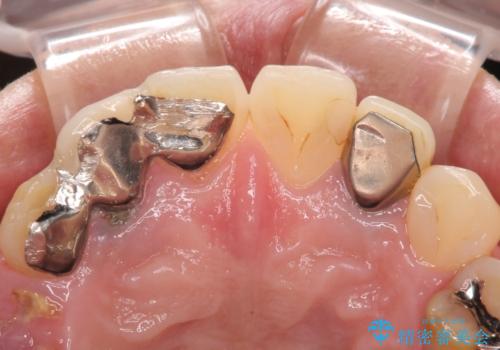

- 歯が破折しているため、抜歯が必要であると近医で診断されてからも放置を続けてしまったとのことで来院された患者様です。

臼歯はもはや咬み合わせに寄与していない状態であり、3歯を抜去してインプラント2本埋入によるブリッジ補綴を計画しました。

セオリーとしては、インプラント補綴治療により奥歯の咬み合わせを確立してから、前歯部の処置を行うことになりますが、初めてのインプラント治療であることや、前歯部の見た目が気になっていることから、前歯の抜歯即時埋入インプラントによる補綴治療を先行して行い、並行して奥歯のインプラント治療を進めて行くこととしました。

臼歯部は前歯以上に炎症が酷く、抜歯即時埋入不可と判断されましたが、従来法よりは短期間で終えることができました。